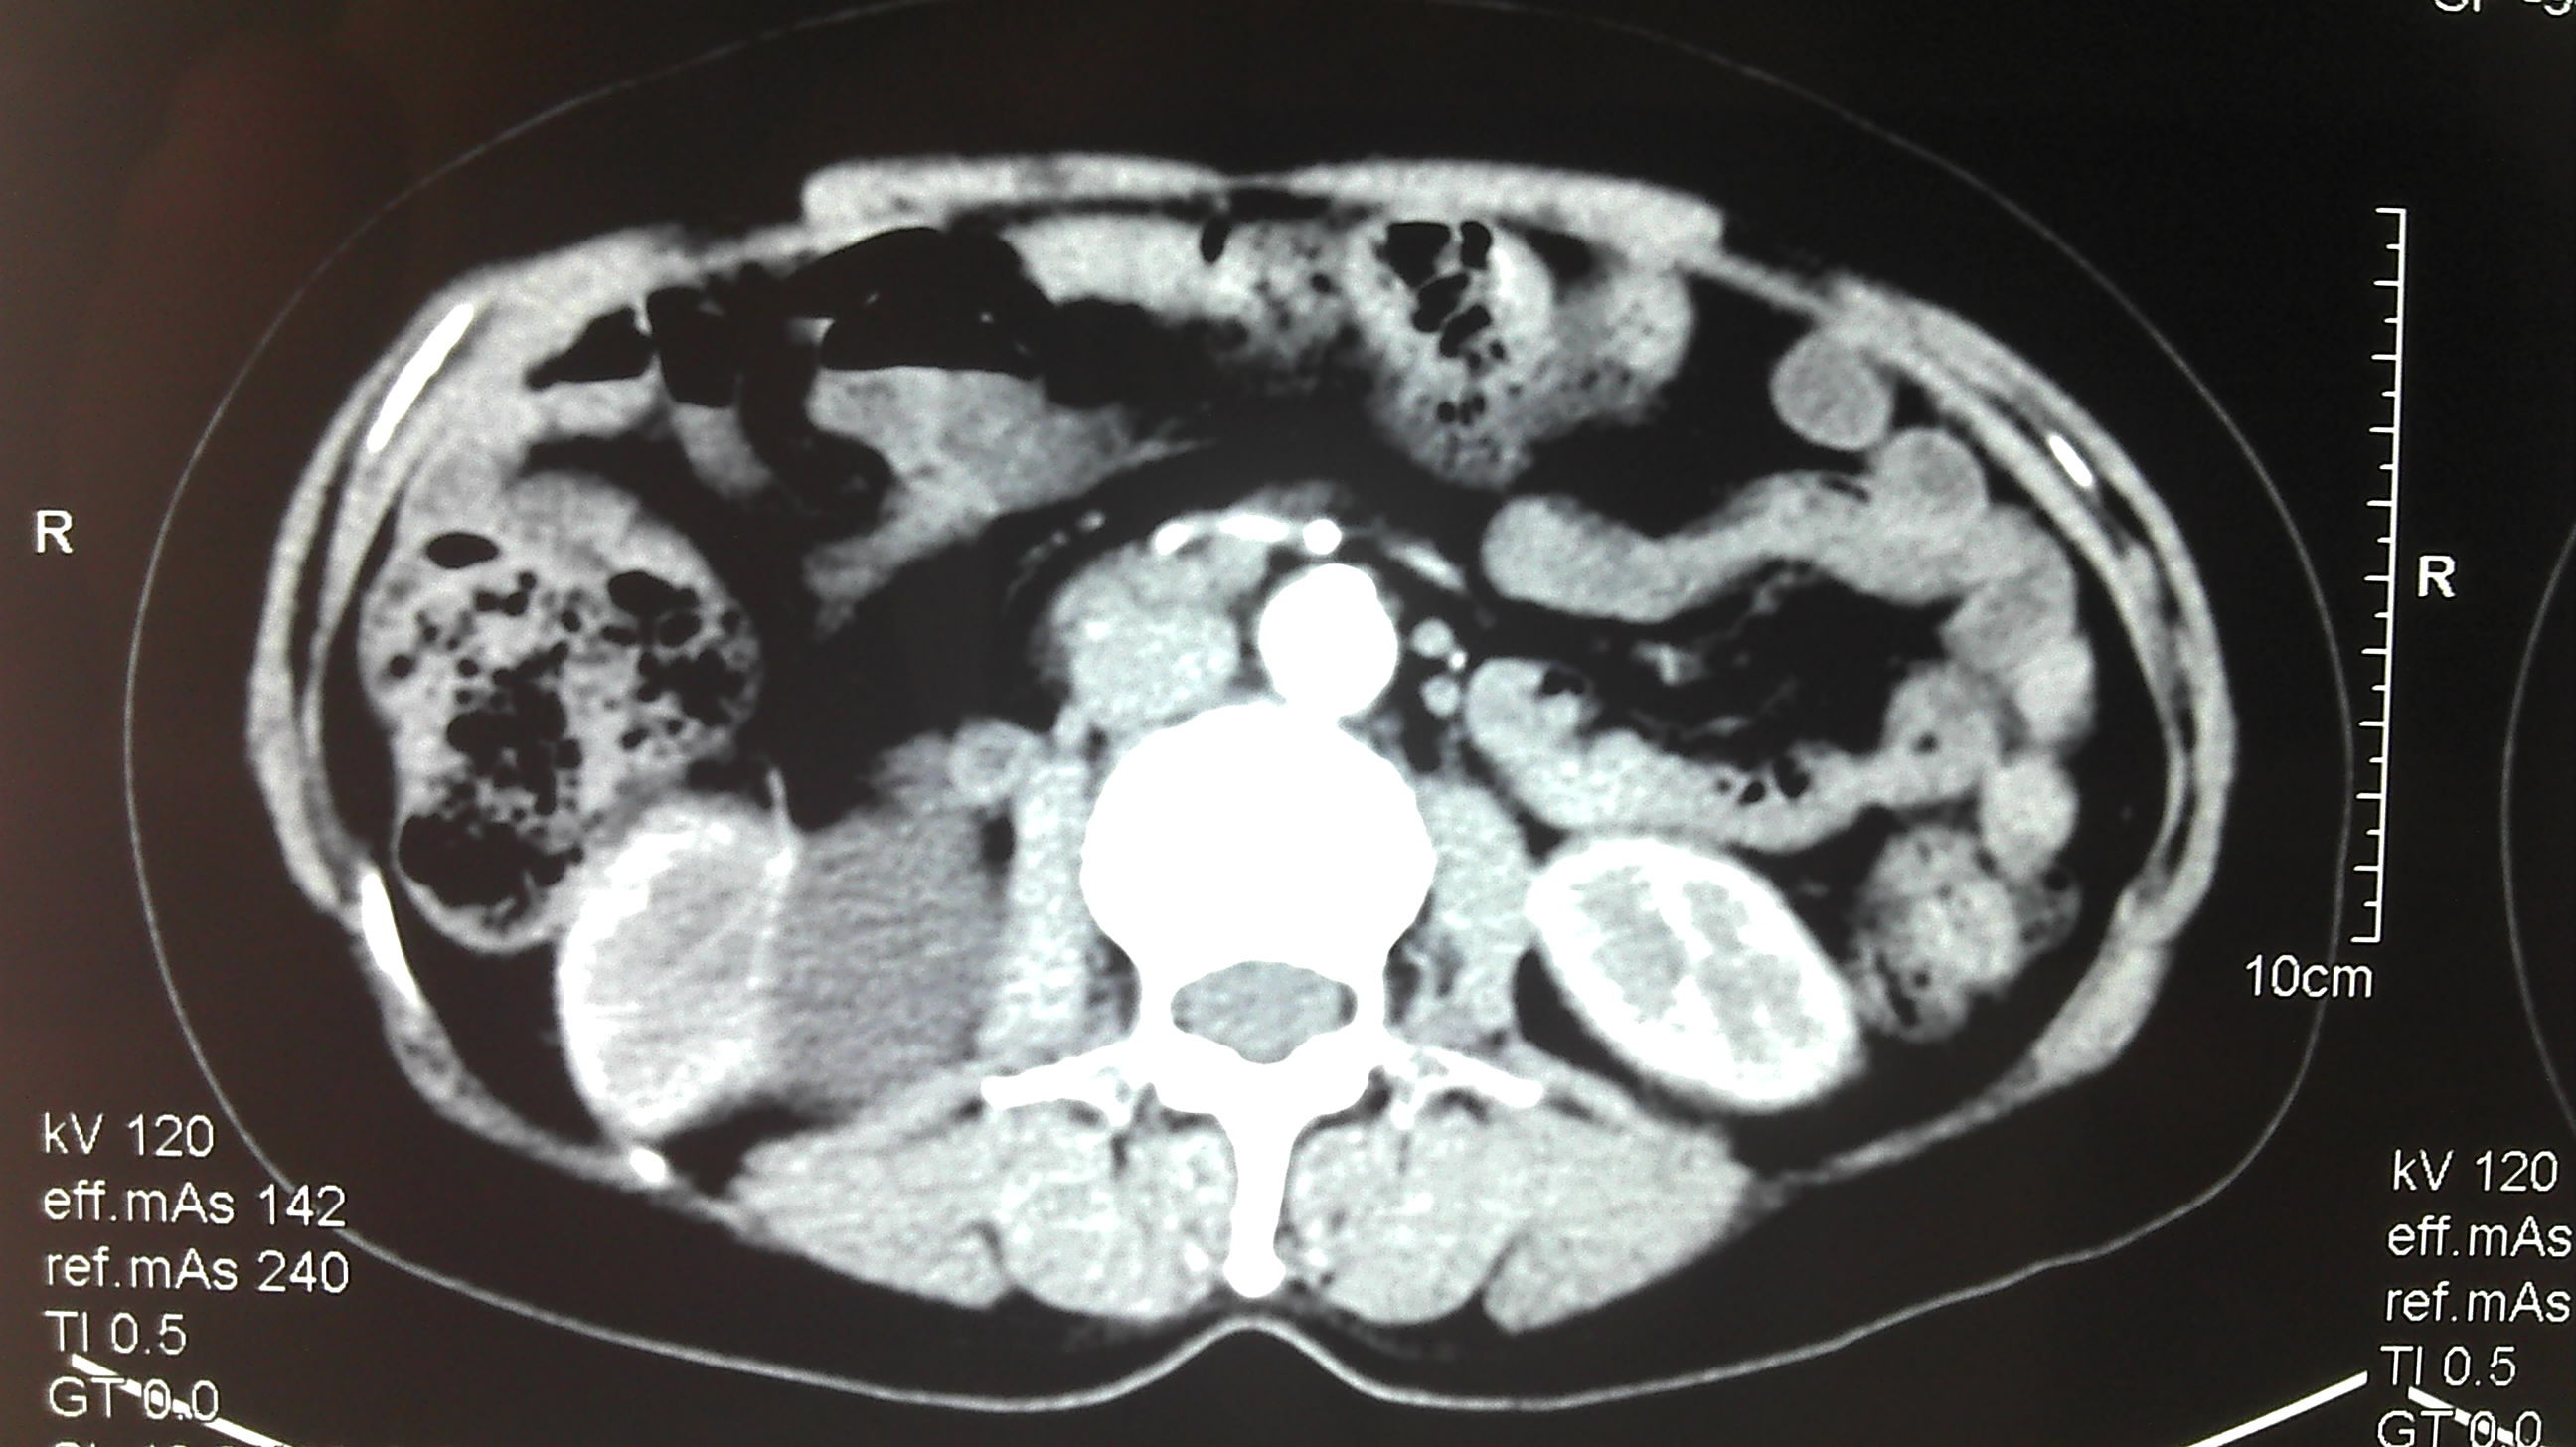

肾盂旁囊肿

肾盂旁囊肿,肾盂囊肿

双肾盂旁囊肿误诊为肾盂积水

肾盂旁囊肿超声

肾盂积水

肾盂分离

肾盂图片